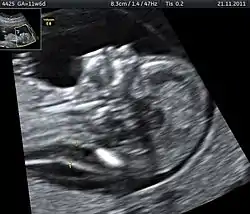

![]() يستخدم تخطيط الصدى غالبا لتشخيص ولادة جنين ميت أو الحالات الطبية التي تزيد مخاطر ولادة جنين ميت. يستخدم تخطيط الصدى غالبا لتشخيص ولادة جنين ميت أو الحالات الطبية التي تزيد مخاطر ولادة جنين ميت. | |